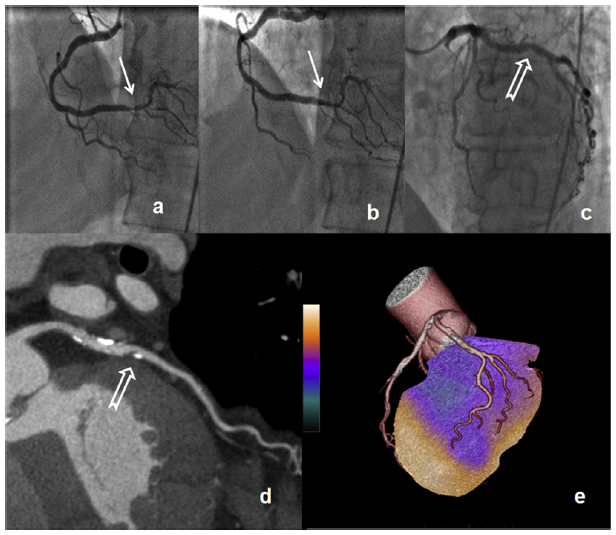

Image

Fig. 8.3 Hybrid methods coronary calcium score (CCS)

The score calculated based on the CT scan - which was taken at the time of the myocardial perfusion SPECT for correction - provides further information about the prognosis of IHD. A higher score indicates higher cardiac risk even if the severity of the perfusion disturbance is the same. (CCS can be assessed when taking a CTCA, but can be done so by itself with low dose radiation for screening.)